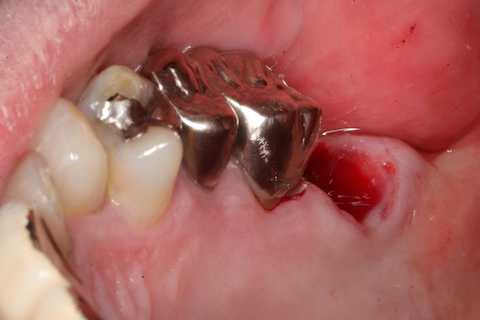

40代男性、左上7、歯根破折

今日は再建した歯を抜歯窩に挿入して固定するまで。

スーパーボンドとCRによる歯牙固定が良いと思う。

また異物の混入等を防ぐための包帯は必要だ。腫脹が治ると隙間ができた食渣等で汚染されるので、1週間後には除去した方が良い。ここではデュラシールを使っている。

隣接歯の接着面には接着性を良くするためにグルーブを形成し、あらかじめスーパーボンドを流しておく。